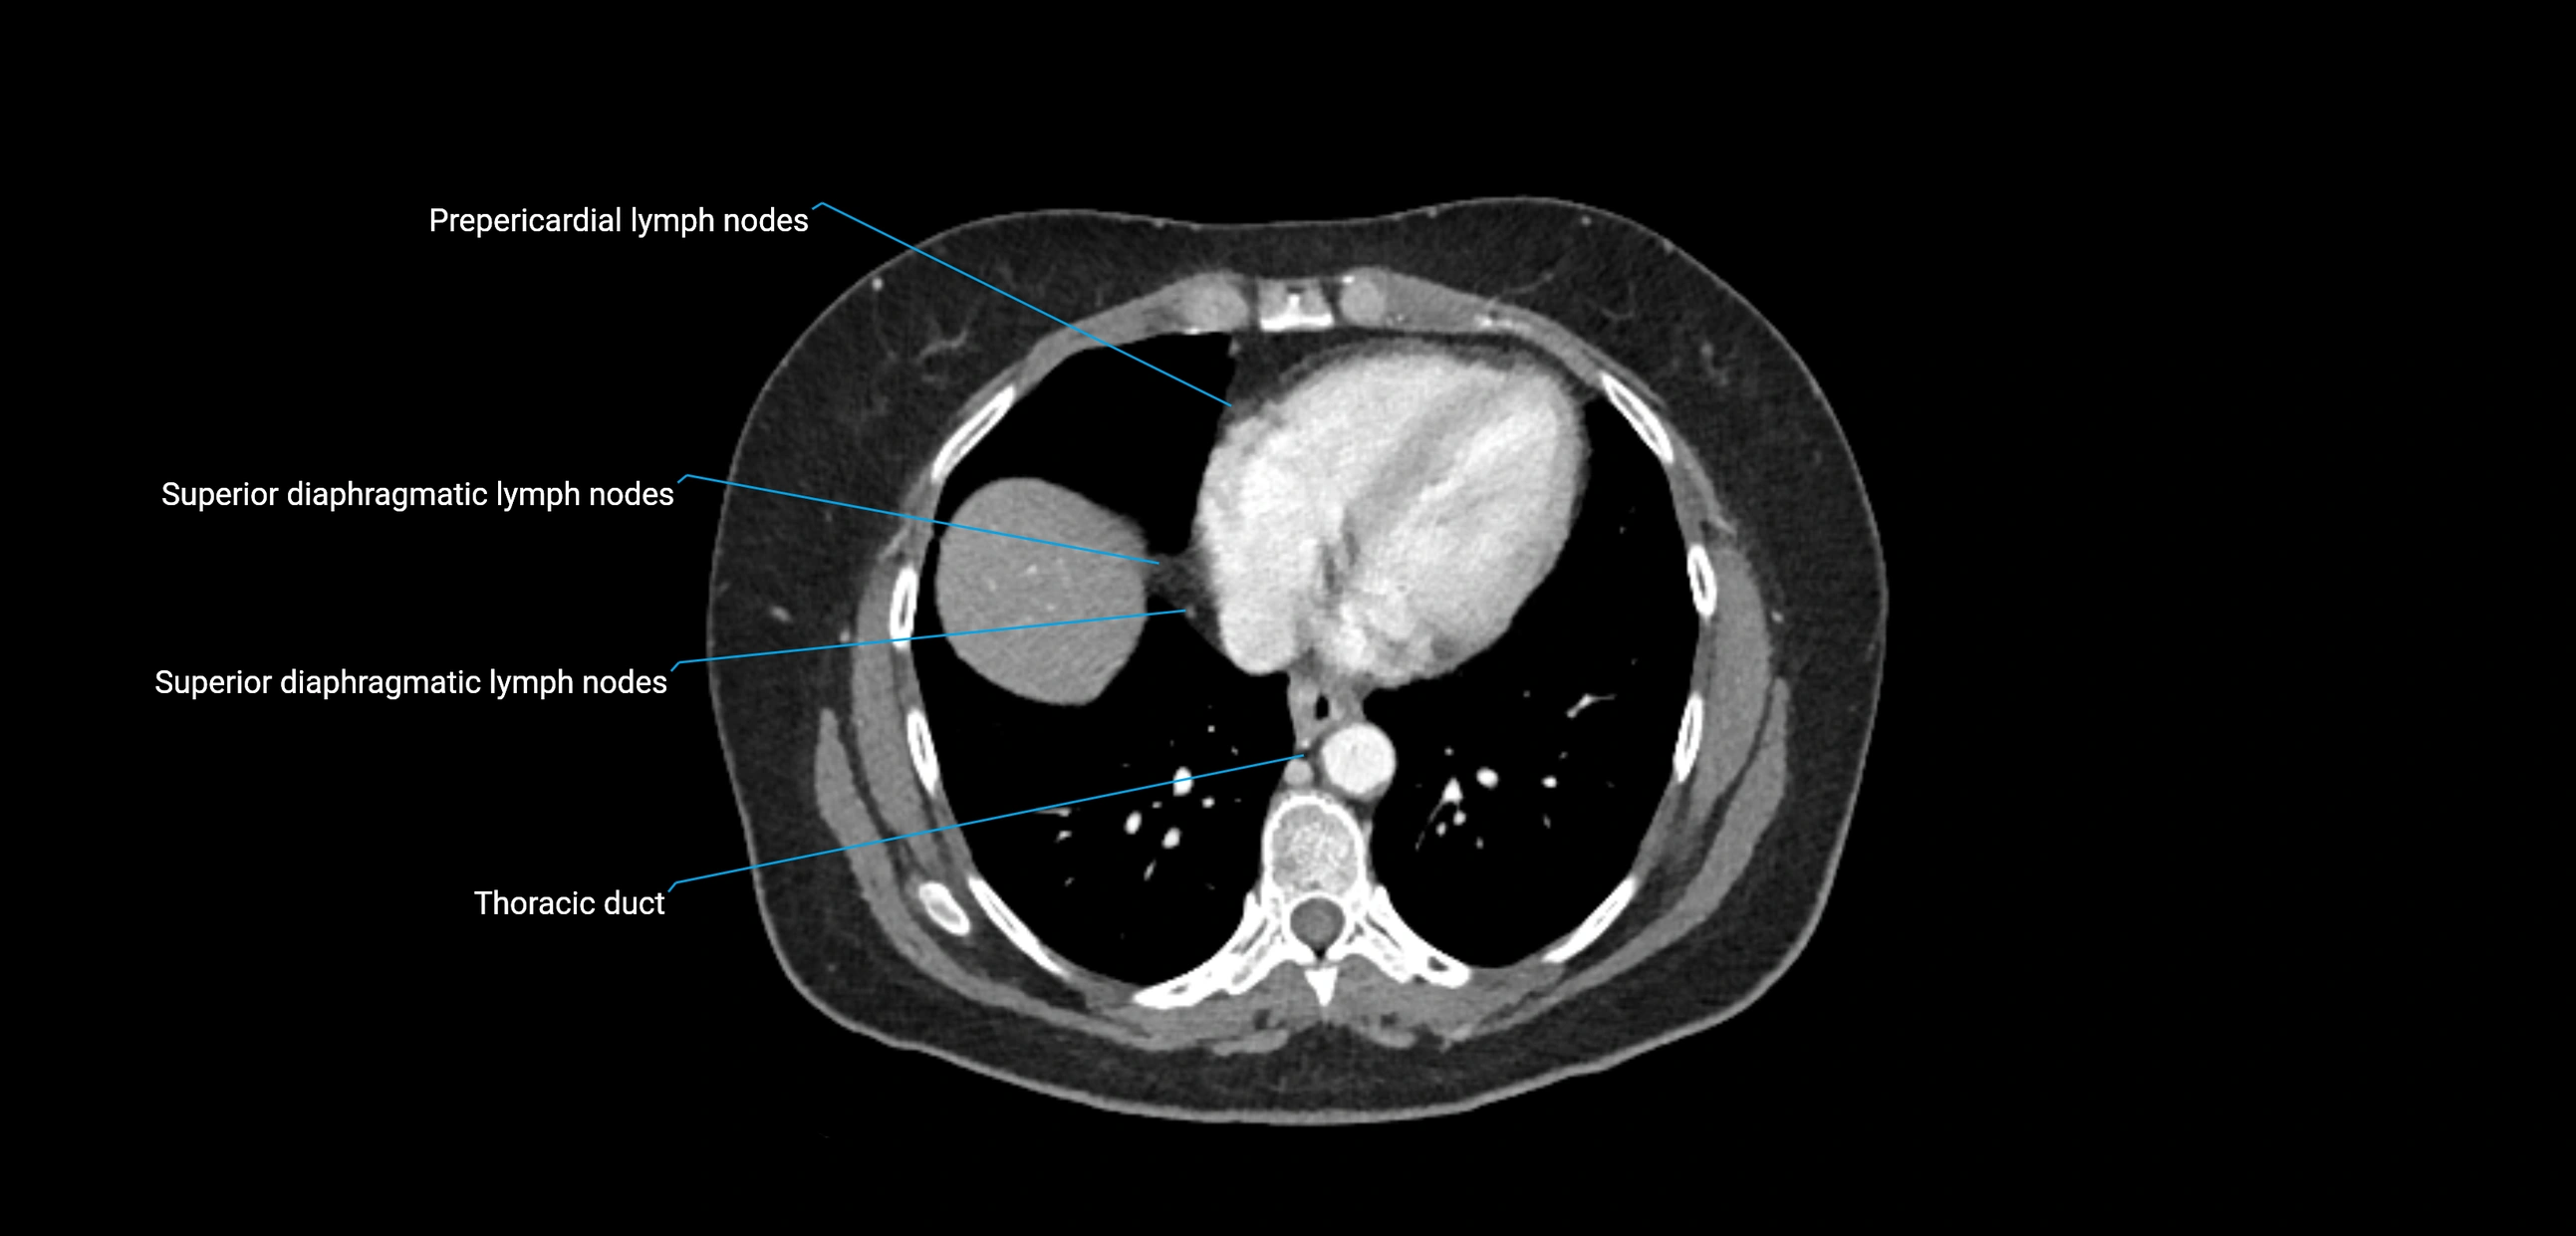

CT Appearance

CT Post-Contrast:

• Normal nodes enhance homogeneously

• Malignant nodes may show heterogeneous enhancement, central necrosis, or conglomerate formation

• Size >1 cm short axis is suspicious, though morphology and distribution are equally important

CT Venography (CTV):

• Demonstrates nodal encasement or compression of adjacent vessels (aorta, IVC, renal veins)

• Useful in staging testicular and ovarian malignancies

• Provides 3D reconstructions for retroperitoneal lymph node dissection planning